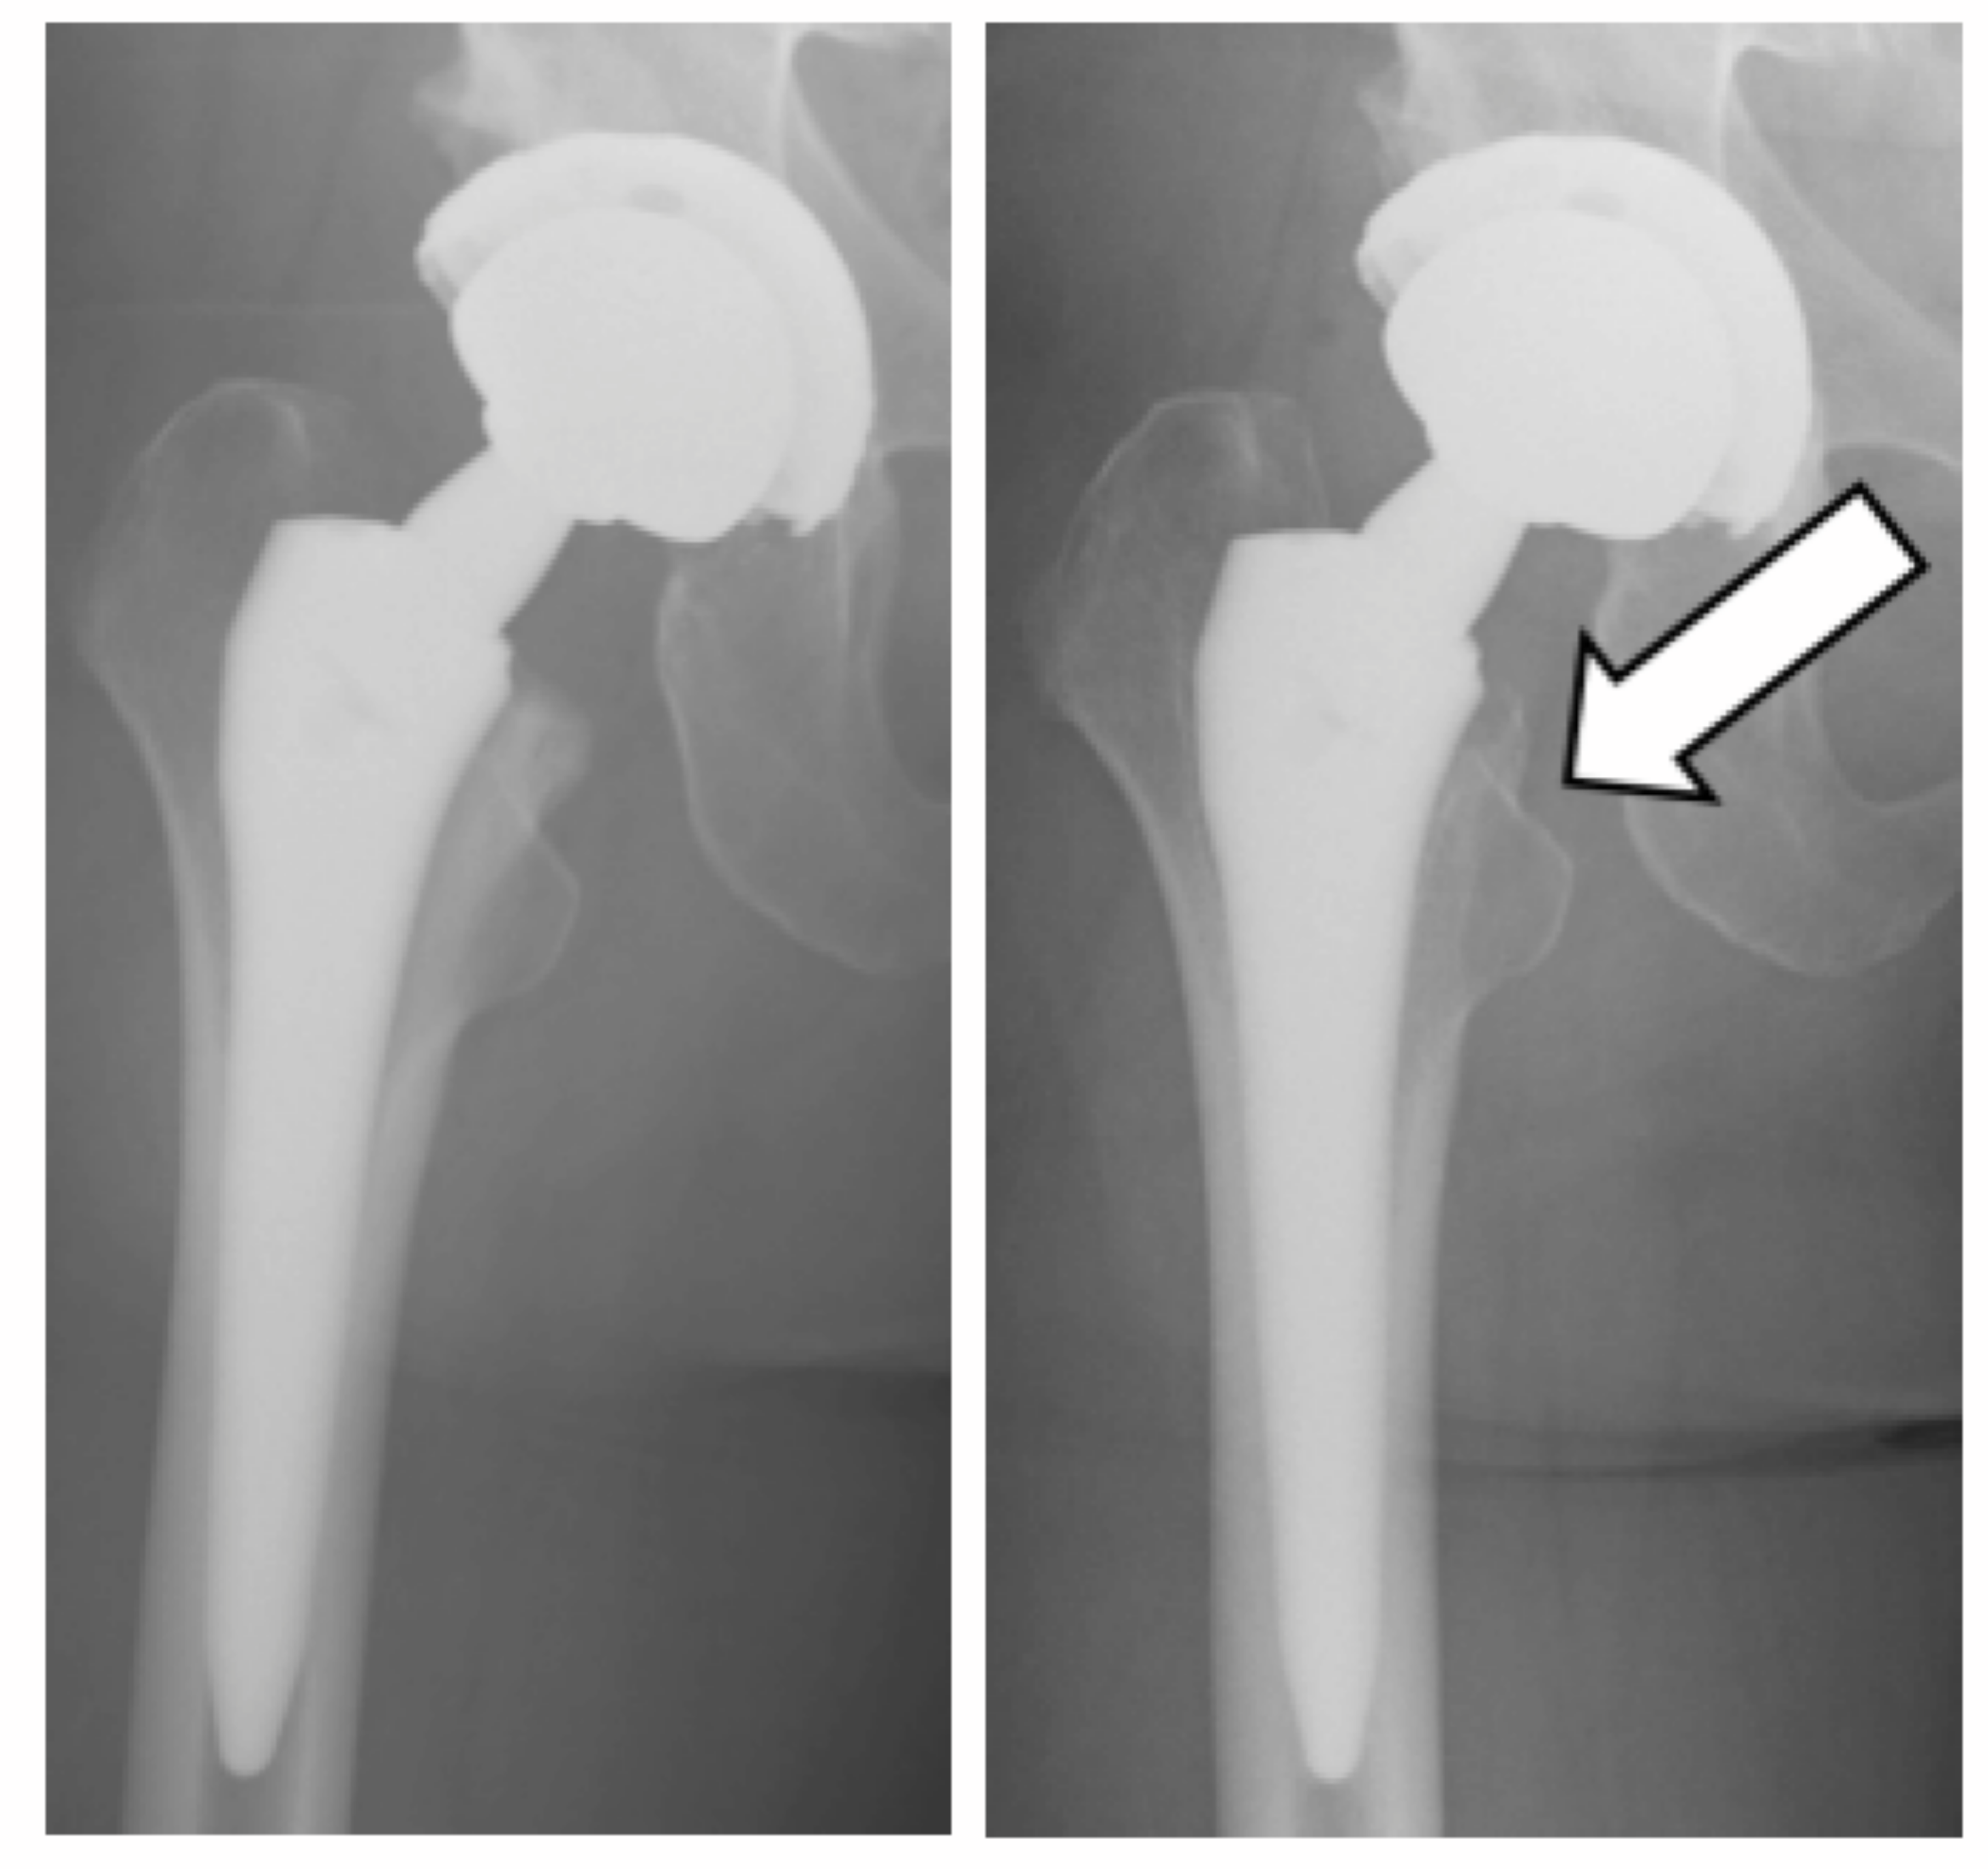

A 49-year-old woman (weight 72 kg, height 156 cm) underwent an uncemented right THA for osteoarthritis of the hip (acetabular implant, 54-mm Trident® acetabular cup (pure titanium) with X3® ultra-high molecular weight cross-linked polyethylene (UHMWXP) insert of 5.8 mm thickness (Stryker Orthopaedics, Mahwah, NJ); femoral implant, Pro femur Z® femoral stem (Ti, 6Al, 4V) with a 4.5° anteverted and 6° varus neck (Ti, 6Al, 4V), and a 40-mm Conserve Plus® short head (CoCr alloy) (Wright Medical Technology; Arlington, TN)) (Figure 1).

Figure 1: Immediate postoperative antero posterior radiograph of the hip at primary THA (A) and 2 years after surgery (B) showing calcar resorption (arrow)

She was reviewed 2 years later and found to have no pain, a normal range of hip motion, and able to fully weight-bear without supporting aids, but she had a clicking and clunking sensation during index hip flexion moment 23 months postoperatively. At the same time, she noticed a soft tissue mass in her right inguinal region. Inflammatory serology was normal. The serum cobalt and chromium ion levels were 2.4 ng/ml and 0.05 ng/ml, respectively. Plain radiographs did not show any impending implant failure, but calcar osteolysis was visible (Figure 1). An ultrasound scan (APLIO XG SSA-790A PLT-805AT, Toshiba Medical Systems Corp., Tokyo, Japan) showed a mixed fluid and solid mass (Figure 2).